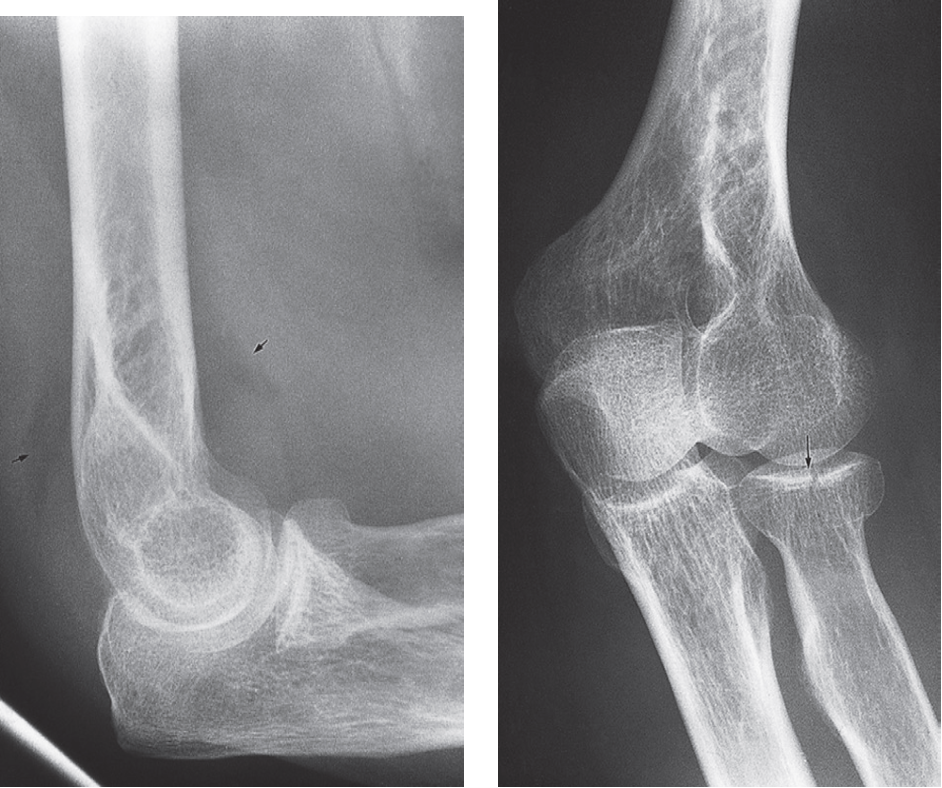

Elbow effusion with fracture of the radial head

Posterior fat pad sign In children suggests a Supracondylar Fractures. In adults, it suggests a radial head fracture.